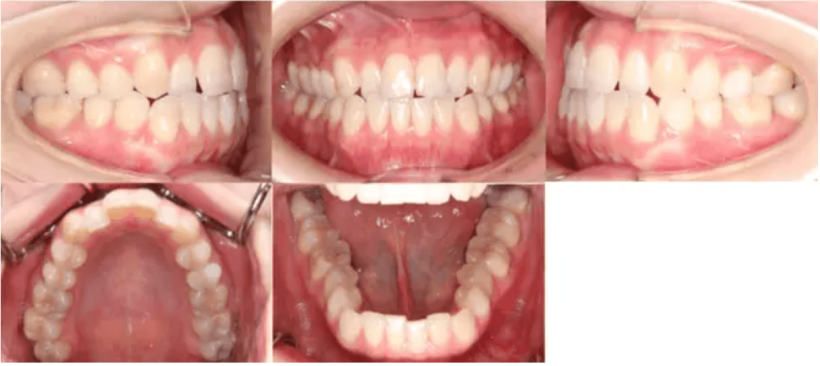

治療内容 前歯に隙間があり、ねじれてしまっていたため、マウスピース矯正で治した。

治療期間 6カ月

費用 40万円

【治療前】

【治療後】